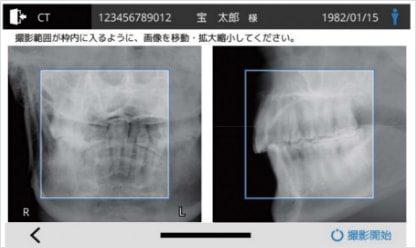

選べる2つのスカウト撮影

カメラスカウト

正面・側面のカメラ映像でFOV位置を設定します。

レントゲンスカウト

CT撮影の前に、X線予備撮影(レントゲンスカウト)を行い、 撮影された正面・側面のレントゲン画像を使用して、FOV位置を設定します。